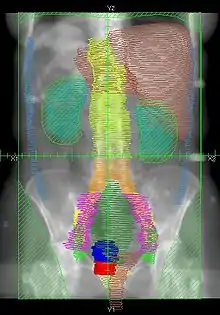

Example of a AP whole abdomen/pelvis radiation therapy treatment field used at Tufts/Brown residency program. Actual patient contours should guide field design.

• Superior border: Above the top of the diaphragm

• Inferior border: Inferior edge of pubic ramus

• Lateral borders: Lateral to peritoneal reflection

• Red: cervix; Blue: uterus; Khaki: bladder; Brown: rectum & liver; Teal: kidney; Light Blue: peritoneal reflection

• Orange: common illiac LNs; Yellow: external illiac LNs; Light Green: obturator LNs; Purple: internal illiac LNs; Dark Green: presacral LNs